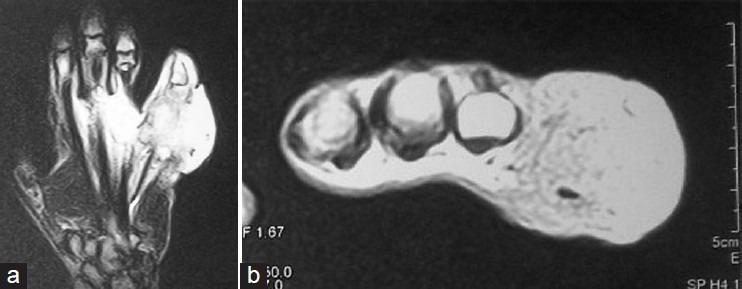

Rhinosporidiosis is a chronic granulomatous disease caused by Rhinosporidium seeberi. It usually affects the mucocutaneous tissue of the nose. Bone involvement is rare. We report a case of Rhinosporidiosis of the nasopharynx which later involved the right little finger where ray amputation was performed.